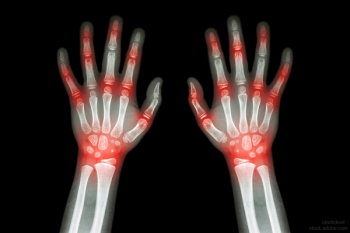

The latest in RA therapies, and what you can expect from the pipeline.